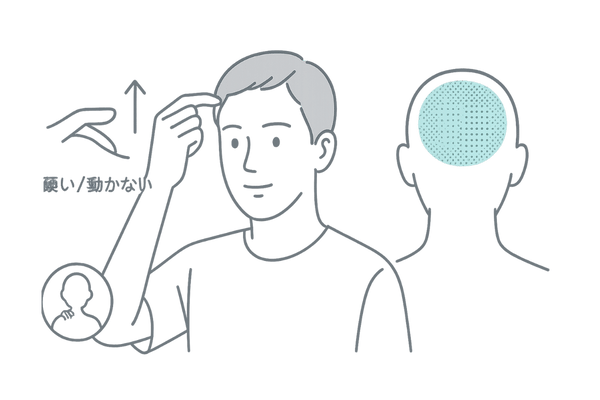

頭皮が硬くなる原因と血行の関係

「頭皮が硬い」と感じることはありませんか。これも血行不良のサインの一つです。

頭皮の下には毛細血管が網の目のように張り巡らされていますが、血流が滞ると頭皮の筋肉(帽状腱膜)が緊張し、柔軟性が失われて硬くなります。

硬くなった頭皮は、血管をさらに圧迫して血行を悪化させるという悪循環を生み出します。柔らかく、指で動かせる頭皮は、血行が良好である証拠です。

サーモグラフィーでは、硬くなっている部位が低温域として示されることがあります。

- 頭皮が硬く、指で動かしにくい